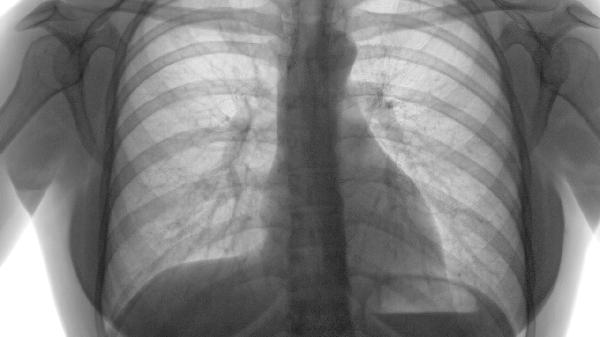

一、呼吸衰竭:最直接的"杀手"

1、肺部功能逐渐丧失

随着肿瘤不断生长,健康肺组织被挤压、破坏,氧气交换能力急剧下降。患者会感到越来越严重的呼吸困难,就像被按在水里无法呼吸一样。